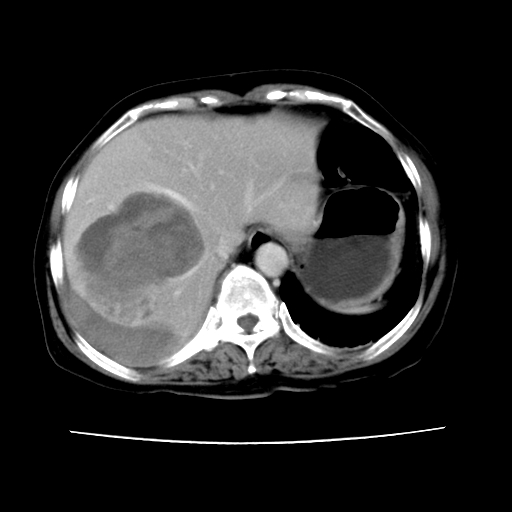

2008-11-10ct平扫(其间去中山医院诊治未行特殊治疗)

2008-11-10ct平扫见并肝内、血膜下血肿基本吸收,肝内低密度灶缩小。此时再做增强ct应有显着意义。对患者/医者都好!

从平扫+增强及治疗后复查片,病变明显缩小,不考虑肝癌出血可能,还是考虑为良性病变可能性大;单纯血肿并包膜下积液吧,病变强化没法解释,肝血管破裂出血吧,增强不符合典型血管瘤的表现,良性肿瘤破裂出血吧,复查片看来好像也不太支持(没做强化也不太好说)。本人还是考虑单纯肝内血肿并包膜下积液,强化是不是血管有外渗。

患者自6月至11月,如果是肝癌,没有经过特殊治疗,想必应该会有所进展吧,而不是ct所见,反而似有病灶减小的趋势。建议增强。